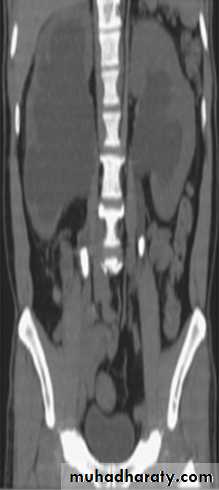

RENAL CELL CARCINOMA(RCC)

Most common malignant renal masses.Spherical or lobulated similar density to the adjacent renal cortex.

May have areas of necrosis.

Enhances heterogeneously and less than that of the adjacent renal parenchyma.

CT is sufficiently accurate so that preoperative biopsy is rarely performed.

Staging is best by CT except for vascular invasion where MRI will be superior.

Staging parameters include : local direct spread, retroperitoneal L.Ns enlargement, liver adrenal or pancreatic metastasis and renal vein or IVC involvement.